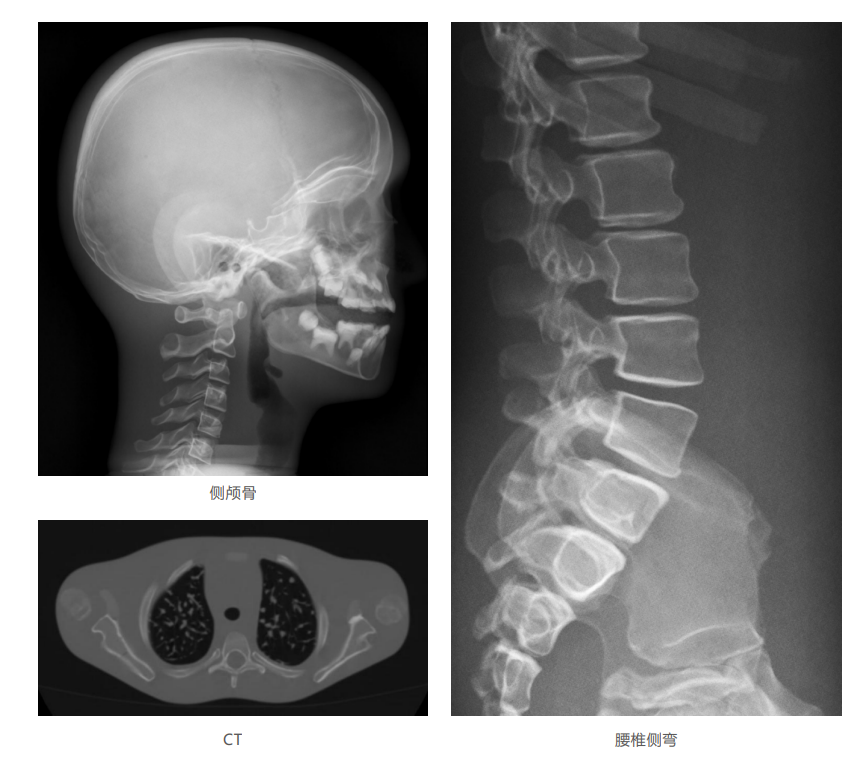

模體掃描成像圖:

仿真兒童培訓模體旨在幫助教學和提高患者對體位、準直和解剖學的理解,其廣泛的特點有助于安全、高質量的兒科影像學的有效指導。 模體的大小和結構都代表了典型的5歲兒童,使其便攜和易于定位。包括頭、胳膊和腿在內的整個身體高110厘米,重20公斤。該系列包括六個部分的模體可單獨或作為一個完整的集合。 右肢有伸直或彎曲兩種配置。左臂和左腿可選伴有或不伴有內嵌骨折。 骨折版本包含最常見的兒科骨折類型,包括脛骨扣帶骨折和腓骨普通骨折;第一跖骨骨折;橈骨切開復位骨折,第二中間趾骨常見骨折。 組件由適當的聚氨酯和環氧材料制成,模擬人體組織的 X射線衰減特性,用于診斷和治療能量范圍(50 keV - 25 MeV) 。 材料經久耐用,耐沖擊,適合連續搬運。透明的軟組織有助于解剖標志的視覺指示。

? 骨骼包含皮質/小梁的區別,生長板和典 型的5歲兒童骨化;